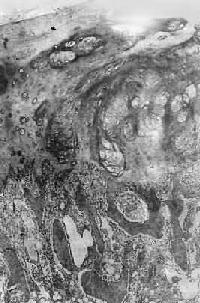

镜下,骨肉由明显间变的梭形或多边形肉细胞组成,细胞大小不等,核形奇异,大而深染,核仁明显,易见病理性核分裂像。肿细胞直接形成肿性类骨组织或骨组织,是诊断骨肉的最重要的组织学依据。所形成的类骨组织或骨组织在不同肿或同一肿的不同部位多少不等。往往可看到肿性骨质发生过程中各阶段的形态,最早期在恶性肿细胞间出现均质红染的胶原样物质,其后红染物质逐渐增多,将肿细胞分隔疏远,构成小梁或片状的肿性类骨组织(图17-8)。类骨组织可伴钙盐沉着,其内的肿细胞固缩变小,形成肿性骨质。骨肉内也可出现肿性软骨(图17-9)。

图17-8 骨肉

多形性肉细胞直接形成肿性骨样组织